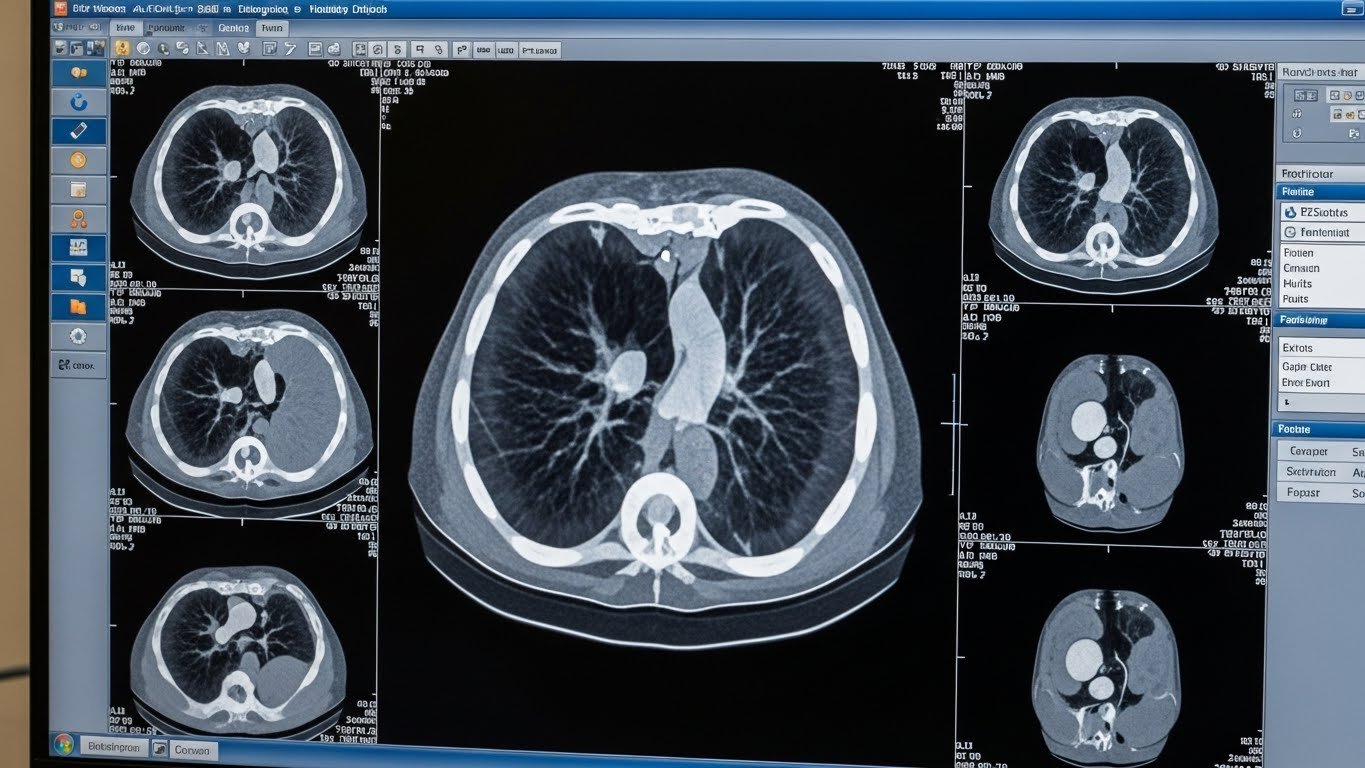

Scanner (Angio-TDM) de l’Aorte Thoracique

Le scanner avec injection de produit de contraste, aussi appelé angioscanner ou angio-TDM, est l’examen de référence pour explorer l’aorte thoracique.

Pourquoi c’est l’examen de choix ?

L’angioscanner présente plusieurs avantages décisifs :

- Rapidité exceptionnelle : l’acquisition des images ne prend que 5 à 10 secondes

- Précision millimétrique : visualisation détaillée de toute l’aorte

- Images 3D : reconstruction tridimensionnelle pour une analyse complète

- Disponibilité : présent dans la plupart des centres de radiologie au Maroc

- Diagnostic d’urgence : idéal pour les situations critiques comme la dissection